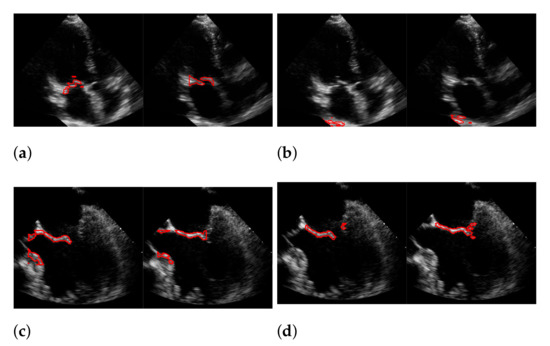

| Recall | Precision | f1-Score | |

|---|---|---|---|

| (a) | 0.494 | 0.692 | 0.565 |

| (b) | 0.44 | 0.558 | 0.45 |

| (c) | 0.165 | 0.551 | 0.244 |

| (d) | 0.378 | 0.43 | 0.377 |